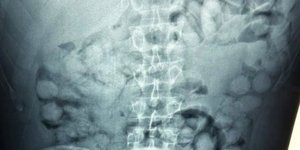

ENGLISH 19/08/2025 08:47 Brazilian Man Arrested at Athens Airport After Swallowing 100 Packets of Cocaine